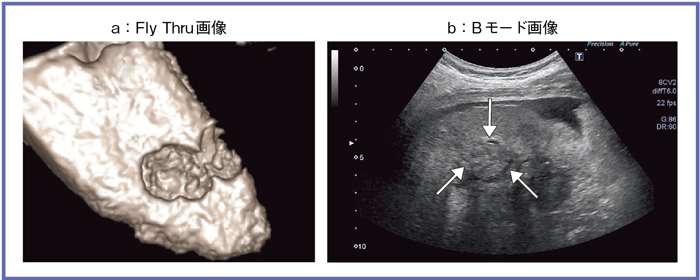

腹水のある症例で肝表面のみを観察するとなると,適応に制限が出てくるため,ある工夫を行った。図8 aは,肝がんの治療部がくぼみとして表現されているが,実はこれは肝表面ではない。Bモード像(図8 b)が示す通り,腫瘍の存在部位は肝臓内部である。

この撮像方法は簡単で,STCをあるレベルまでゼロにすると,信号がなくなり,仮想の腹水域を作ることができる(図9)。さらに,造影を加えると,肝臓自体は造影され,治療部は造影されないことから,図8aのような画像を得ることができる。肝硬変の症例でも,造影を加えることで,STC調整で人工的に作成した断面に存在しうる凹凸を表現することができる(図10)。このような工夫を施すことで,Fly Thruの適応が広がるものと考える。

図8 肝臓内部へのFly Thruの応用(肝がん治療部)